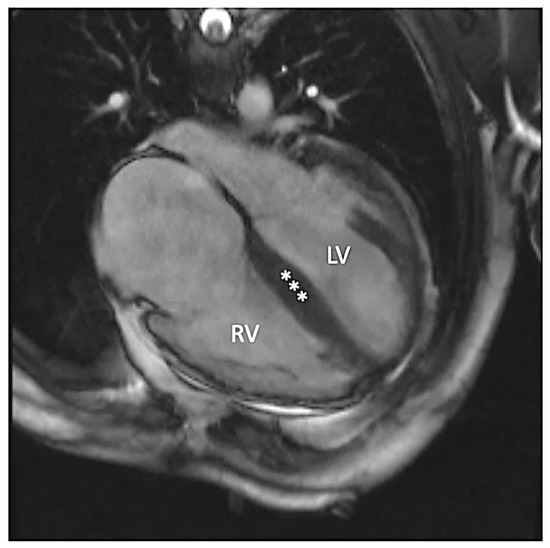

Figure 2.

Steady-state free precession four-chamber image demonstrating enlarged left (LV) and right (RV) ventricles. Additionally, increased myocardial thickness in the septal segments (asterisks) and wall thinning of lateral segments of the left ventricle are seen.